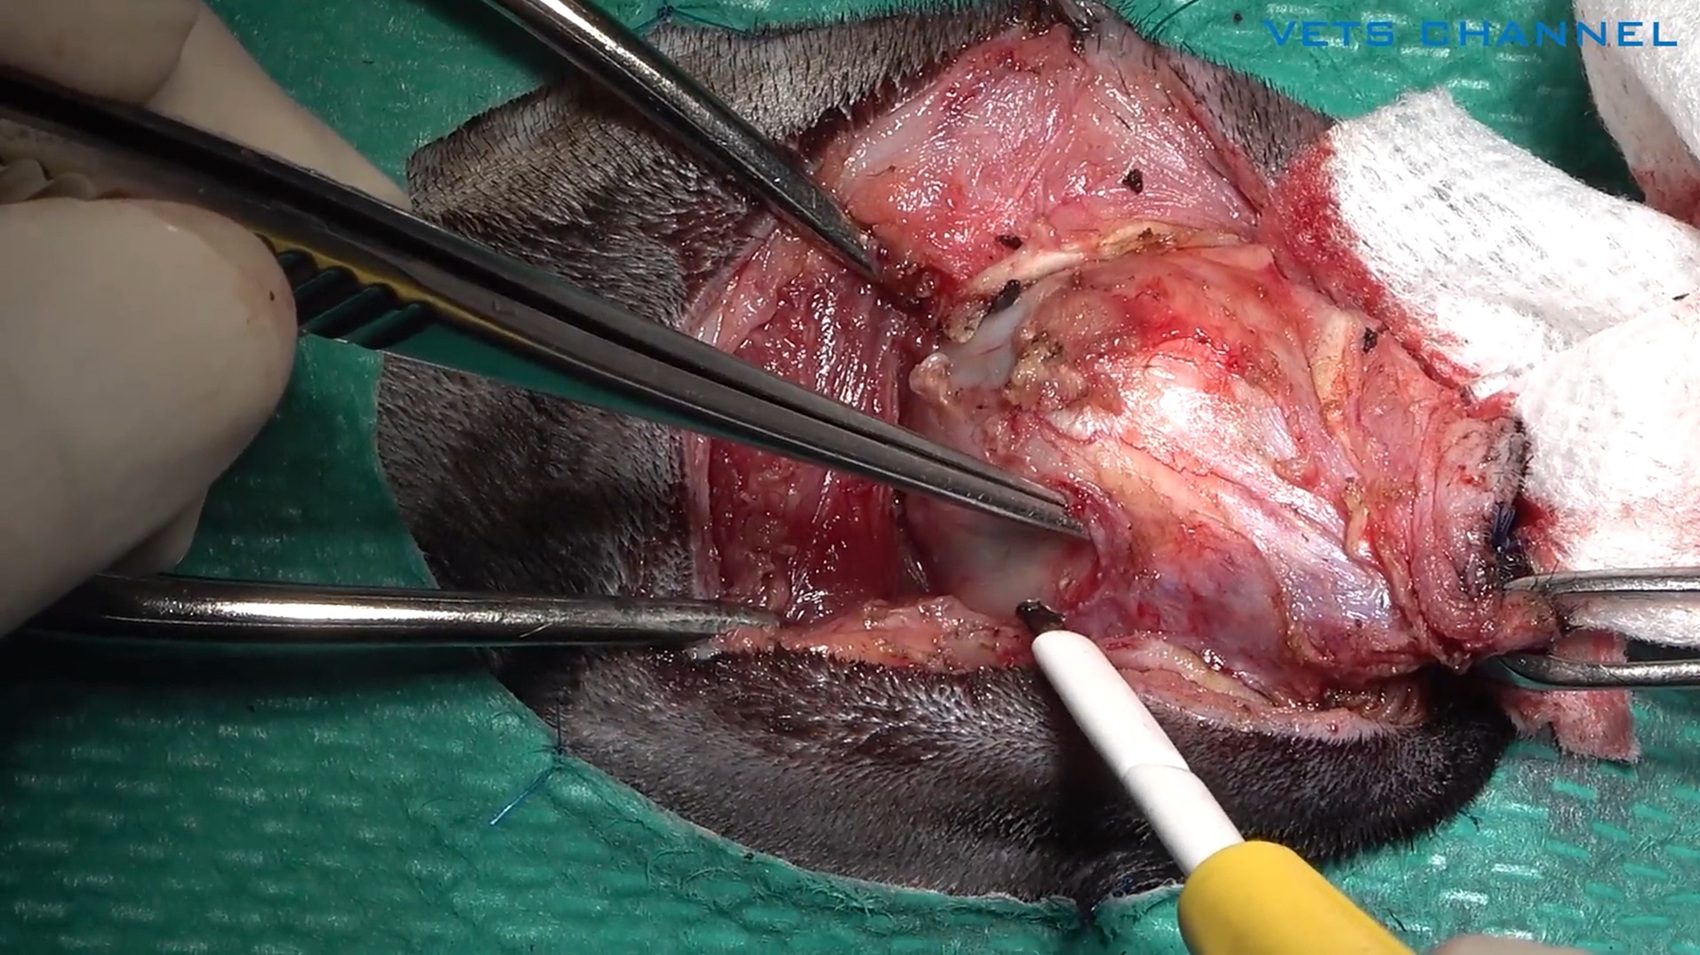

局所再発した扁平上皮癌に対する両側下顎切除術

藤本 晋輔先生 (大津どうぶつ医療センター)

20分

2025/11/14

局所再発した扁平上皮癌に対する両側下顎切除術

藤本 晋輔先生 (大津どうぶつ医療センター)

20分

2025/11/14